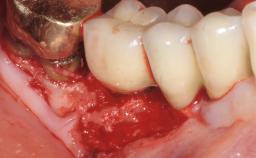

A 37-year-old male patient was referred to the Department of Periodontology at the University of Bern, Switzerland, by a private dentist. Tooth 21 had been lost due to trauma and had been replaced with an implant and a cemented single crown. The tapered-effect tissue-level implant had a diameter of 4.1 mm, a length of 12 mm, and a sandblasted and acid-etched (SLA) surface (Straumann Dental lmplant System; Institut Straumann AG, Basel, Switzerland). The metal-ceramic crown had been cemented permanently, leaving a submucosal gap between the implant shoulder and the crown margin. Absence of marginal bone loss apical to the polished transmucosal neck of the implant could be observed .